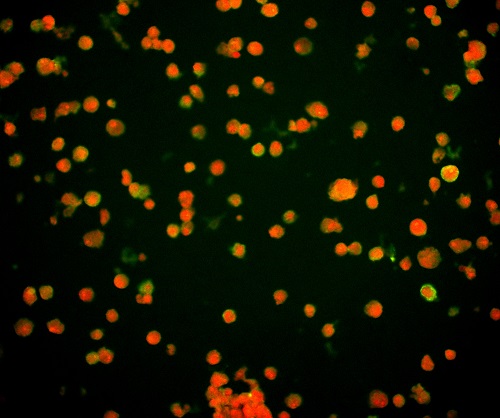

(1)通過觀測對病毒進(jìn)行特異性標(biāo)記產(chǎn)生的熒光信號,從而實(shí)現(xiàn)對病毒位置數(shù)量的判斷。病毒主要由核酸和蛋白質(zhì)組成,常見的一種方法是利用熒光標(biāo)記的特異核酸探針與病毒含有的靶DNA分子或RNA分子進(jìn)行雜交,可通過在熒光顯微鏡下觀察熒光信號,來確定與特異探針雜交后被染色的病毒的分布和數(shù)量,這種方式也稱為原位熒光雜交技術(shù)(FISH)。

FISH做的病毒檢測,紅色為病毒外殼蛋白

(引自公開論文https://doi.org/10.1073/pnas.1820132117)